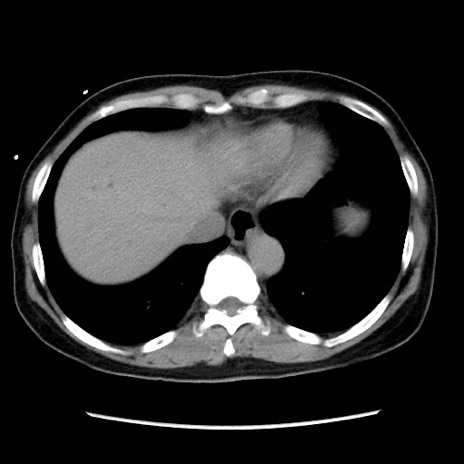

症例10(横断像)

【症例】 50歳代女性

【主訴】 腹痛

【現病歴】前日生レバーを食べた。今朝に排便あり。 昼前に突然発症の腹痛を生じ、当院救急外来を受診した。

【身体所見】 意識清明、腹部:平坦、軟、下腹部やや左を中心に圧痛・反跳痛あり、筋性防御あり